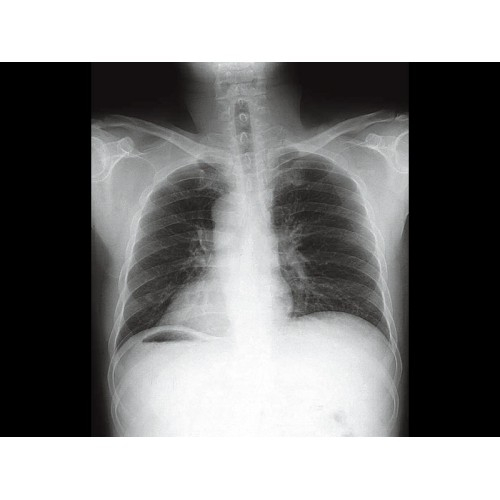

Профессиональный стационарный рентген GE XR 6000 представляет собой современное диагностическое оборудование премиум-класса. Аппарат разработан для проведения широкого спектра рентгенологических исследований с высочайшей точностью и детализацией изображений.

- Диагностики заболеваний органов грудной клетки

- Обзорной и прицельной рентгенографии всех анатомических областей